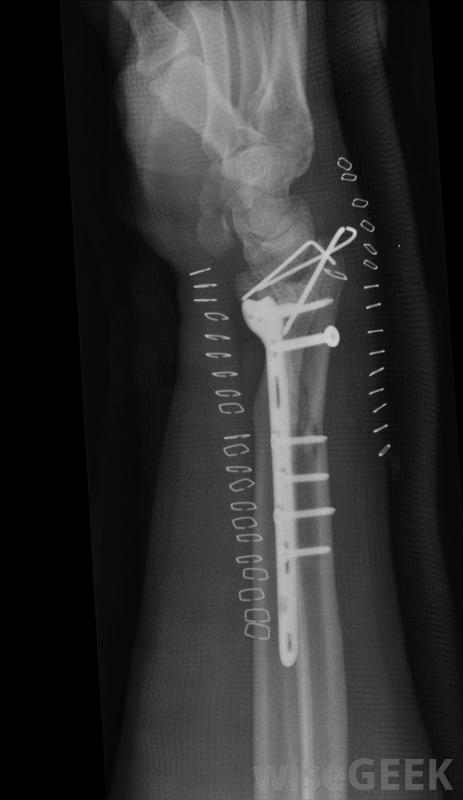

三踝骨折是踝關節骨折的一種類型。在踝關節的內側,脛骨或脛骨的下端形成一個稱為內踝的骨結節。小腿外側有一塊稱為腓骨的較薄的骨頭,在末端形成一個稱為外踝的腫塊,或第三踝,是由脛骨下端后部的一個骨唇形成的。當踝關節骨折涉及三個踝關節時,稱為三踝骨折,通常需要手術將骨折固定在一起,同時愈合跌倒是老年人三踝骨折的常見原因,可能是由于摔倒、突然扭傷或扭傷腳踝引起的。也可能是車禍造成的,以及其他小腿受傷。由于踝關節由許多不同的骨骼組成,踝關節骨折的嚴重程度從一塊骨頭的裂縫到幾塊骨頭的斷裂,有時刺穿皮膚疼痛,腫脹,瘀傷,可能會出現畸形,腳踝可能無法承受重量。跌倒可能導致三踝骨折如果在檢查可能骨折的踝關節時發現這些癥狀,可能會懷疑骨折。然后可以進行X光檢查,以提供準確的診斷。在某些情況下,只有內踝或外踝可能骨折。如果骨骼不太遠,骨折被認為是穩定的,這意味著骨折會繼續存在當骨頭重新排列時,可能不需要手術,治療可能包括石膏或夾板。如果是三踝骨折或雙踝骨折,內踝和外踝骨折,則損傷通常不穩定,通常需要手術三踝骨折可導致瘀傷。三踝骨折的外科治療通常包括使用當骨折愈合時,用來固定骨折的金屬板、螺絲釘或金屬絲。在骨折牢固融合在一起之前,腳踝不可能承受重量,這可能需要四個月的時間,在這段時間里可以拍X光片來檢查骨骼是否沒有移位,一旦有可能移動腳踝,建議進行一系列的鍛煉來加強關節周圍的肌肉通常會對骨折進行X光檢查三踝骨折的外科治療通常包括使用金屬板和螺釘或金屬絲將骨折固定在一起鞋子有助于防止許多三踝骨折。腳踝骨折可能是由于突然轉動腳踝造成的在腳上放置石膏可能是治療三踝骨折的一部分。